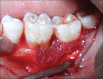

Periodontal regeneration is defined as the reproduction or reconstitution of a lost or injured part to restore the architecture and function of the periodontium. The ultimate goal of periodontal therapy is to regenerate the lost periodontal tissues caused by periodontitis. The most positive outcome of periodontal regenerative procedures in intra bony defect has been achieved with bone grafts. For complete regeneration, delivery of growth factors in a local environment holds a great deal in adjunct to bone grafts. Platelet rich fibrin (PRF) is considered as second generation platelet concentrate, consisting of viable platelets, releasing various growth factors. Hence, this case report aims to investigate the clinical and radiological (bone fill) effectiveness of autologous PRF along with the use of alloplastic bone mineral in the treatment of intra bony defects.